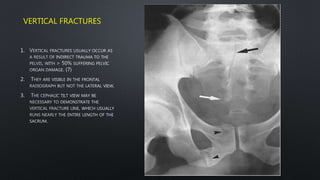

VERTICAL FRACTURES

1.

2.

3.